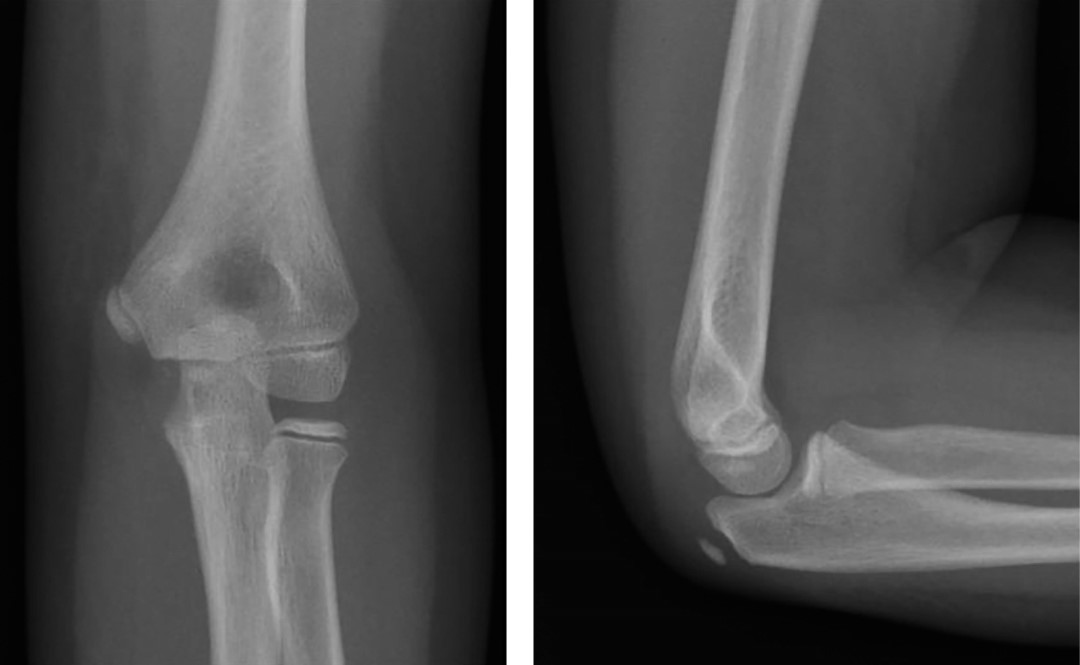

Figura 3